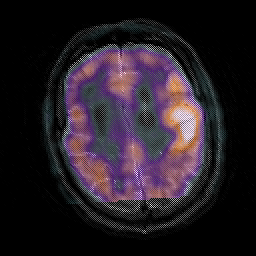

Subacute Stroke, overlay -- Slice #18

[Home][Help][Clinical] Slice 18